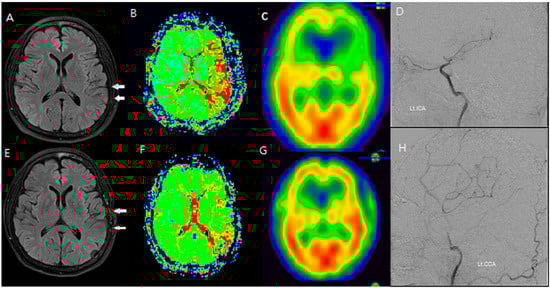

Additionally, changes in the ivy sign on MR FLAIR images were compared with MR perfusion images. The degree of change in mean transit time (MTT) was greater in areas with positive or minimal HV compared to areas with negative HV. After STA-MCA bypass surgery, regions where HV decreased or disappeared showed improved hemodynamics, as reflected in both SPECT and MR perfusion imaging (Figure 2), and this correlation between HV regression and improved cerebral perfusion was similarly observed in a patient with distal ICA stenosis (Figure 3).

Figure 3. An F/66 patient with left distal ICA severe stenosis. (AD) Preoperative MR FLAIR, perfusion MR, and SPECT images show prominent hyperintense vessels (white arrows) in cortical regions with a reduced CVR. (EH) Postoperative imaging reveals the disappearance of HV and improvement in cerebral perfusion, indicating successful revascularization via STA-MCA bypass. HV regression corresponded to an increased CVR and reduced perfusion delay, reinforcing the functional significance of FLAIR findings.